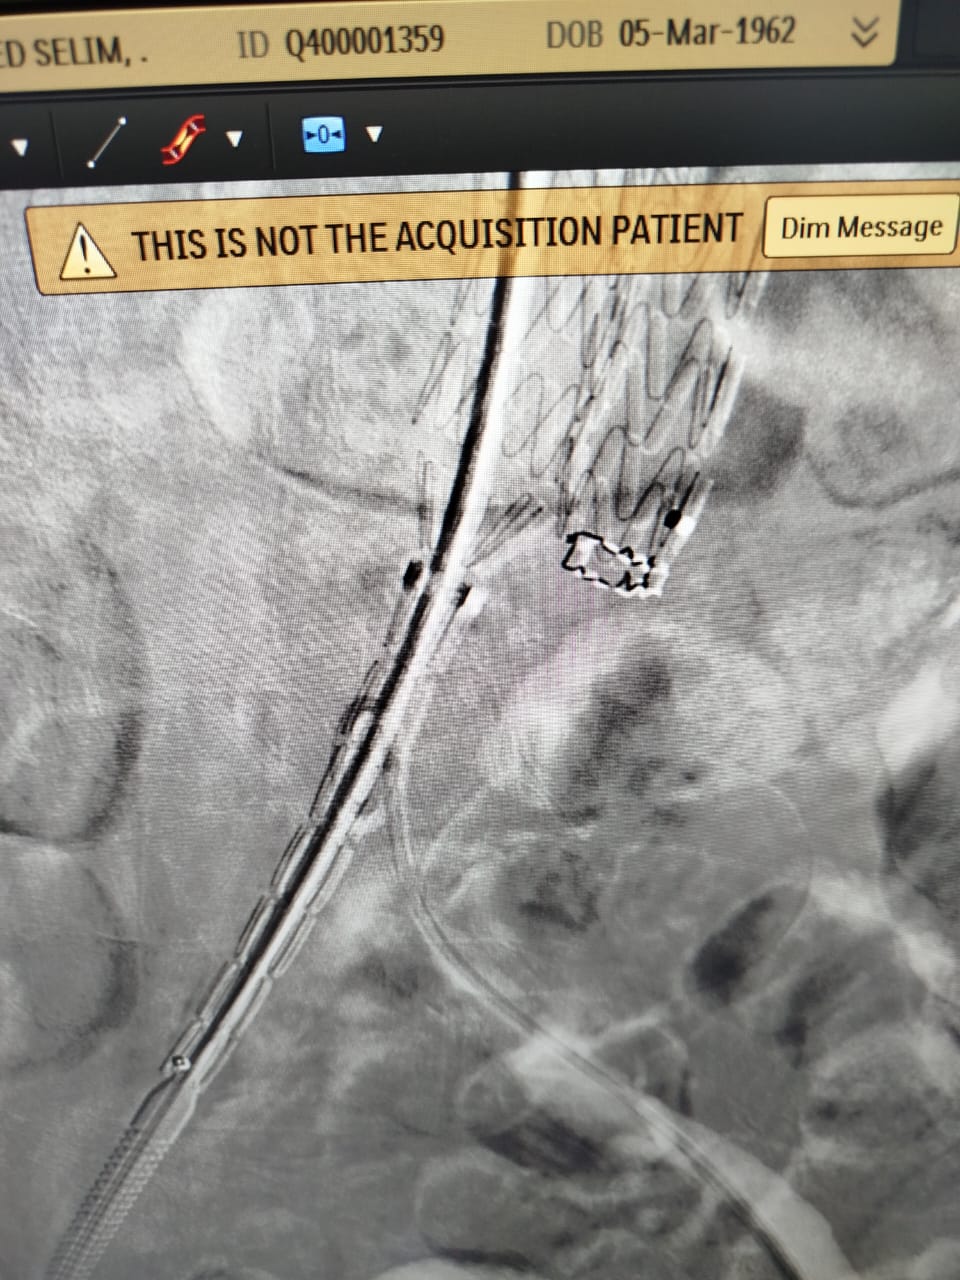

أعلنت الهيئة العامة للرعاية الصحية، عن نجاح أول عملية لعلاج تمدد الشريان الأورطي باستخدام الدعامة المغطاة بتقنية EVAR، لسيدة  مسنة، وذلك داخل مستشفى شرم الشيخ الدولى ، التابع لهيئة الرعاية الصحية بجنوب سيناء.

وأوضح بيان الهيئة، أن المريضة حضرت إلى مستشفى شرم الشيخ الدولى، وبمناظرة الحالة تم اكتشاف وجود تمدد الشريان الرئيسى للقلب (الشريان الأبهر ) للمريضة، وعليه تم عرض الحالة على قسم جراحة الأوعية الدموية، ووجد أن نسبة حدوث انفجار الشريان لهذه المريضة  تتخطى 80%، ووفقًا للبروتوكولات العلاجية أوصى الفريق الطبي المعالج بإجراء عملية لإصلاح تمدد الشريان الأورطي الباطني بتقنية (EVAR) للمريضة.

وتابع البيان: تم إجراء العملية للمنتفعة بنجاح، وبدون أي مضاعفات ، وذلك على يد فريق طبي من أمهر الاستشاريين بمستشفى شرم الشيخ الدولى ضم كل من،  "أ.د احمد رياض ، أ.د شريف حسين" استشاريى جراحة الأوعية الدموية بالمستشفى ، وبمشاركة فريق التخدير برئاسة أ.د إسماعيل عبد الجواد استشاري التخدير ، وبمعاونة فريق التمريض المتميز بمستشفى شرم الشيخ الدولى.

مشيرًا أن منشآت الهيئة، بما في ذلك المستشفيات ومراكز ووحدات صحة الأسرة، تُجهز وفق أعلى المعايير العالمية من حيث الإنشاء والتقنيات الطبية الحديثة، وأوضح أن استخدام تقنيات متطورة مثل تقنية EVAR لعلاج تمدد الشريان الأورطي بدون جراحة، يمثل خطوة نوعية نحو تقليل المخاطر الجراحية وتسريع فترة التعافي، فضلًا عن ضمان العلاج الآمن وفق أحدث الإرشادات  الطبية والبروتوكولات العلاجية الدولية.

جدير بالذكر، أن استخدام الدعامة المغطاة EVAR من أحدث العلاجات المتوفرة عالميًا لعلاج تمدد الشريان الأورطي، وقد تم استحداثها ضمن حزم خدمات منظومة التأمين الصحي الشامل الجديدة ، حيث توفر عدة مزايا منها استخدام نوع تخدير أبسط ويظل المريض مدة أقل تحت تأثير المخدر، مع عدم الاحتياج لنقل دم، وعدم الاحتياج للبقاء في العناية المركزة، سرعة العودة للمنزل بعد يوم واحد من العملية مقارنه بعشرة أيام علي الأقل في حالة الفتح الجراحي.